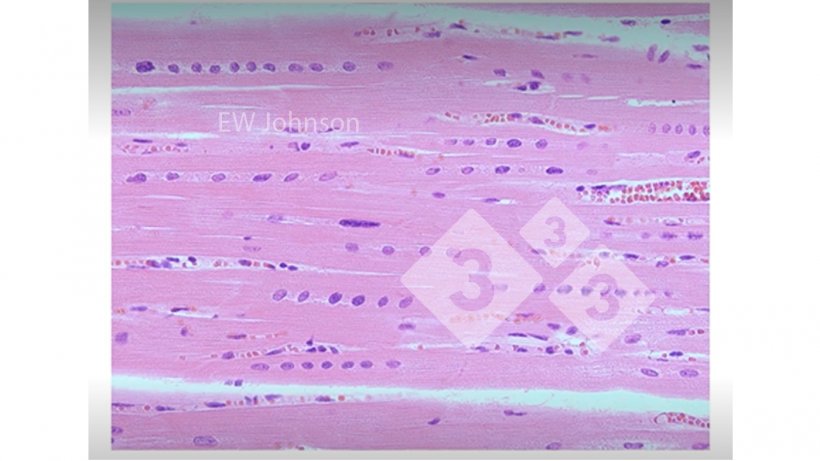

Czasami możemy znaleźć rzeczy, których nie spodziewaliśmy się zobaczyć. (Fot. 3)

Fot. 3: Mięsień sercowy z krwotokiem, martwicą hialinową i liniowe ułożenie jąder komórkowych, co wskazuje na niedobór witaminy E i selenu. Świnie te nie mogą mieć normalnie funkcjonującego układu odpornościowego.